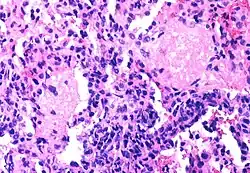

Pneumocystis jiroveci pneumonia

Mycobacterium avium complex

The diseases associated with AIDS, such as Pneumocystis jiroveci pneumonia (PCP) and Mycobacterium avium complex (MAC), are not caused by HIV, but rather result from the immunosuppression caused by HIV disease. As the immune system of an HIV-infected individual weakens, he or she becomes susceptible to the particular viral, fungal, and bacterial infections common in the community. For example, HIV-infected people in the Midwestern United States are much more likely than people in New York City to develop histoplasmosis, which is caused by a fungus. A person in Africa is exposed to pathogens different from individuals in an American city. Children may be exposed to different infectious agents compared to adults.[87]

HIV is the underlying cause of the condition named AIDS, but the additional conditions that may affect an AIDS patient are dependent upon the endemic pathogens to which the patient may be exposed.